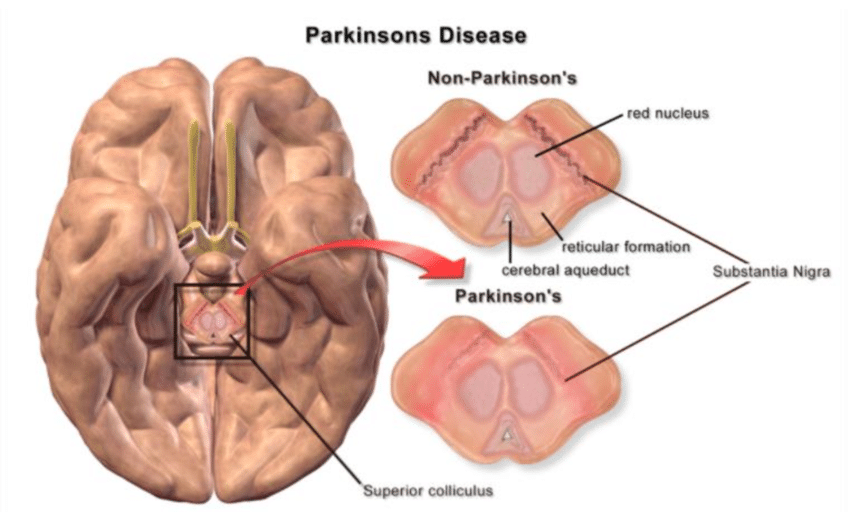

Substância negra, suas funções no cérebro e a relação com a Doença de Parkinson.